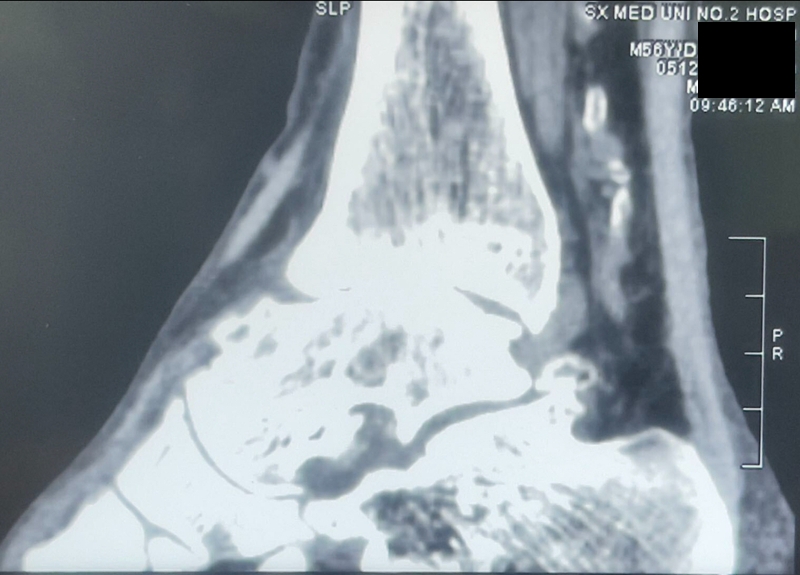

病例报告之二,xx,男,56岁,左踝创伤性关节炎。左踝崴伤6年,疼痛加剧3年。切口显露同前。

手术前资料